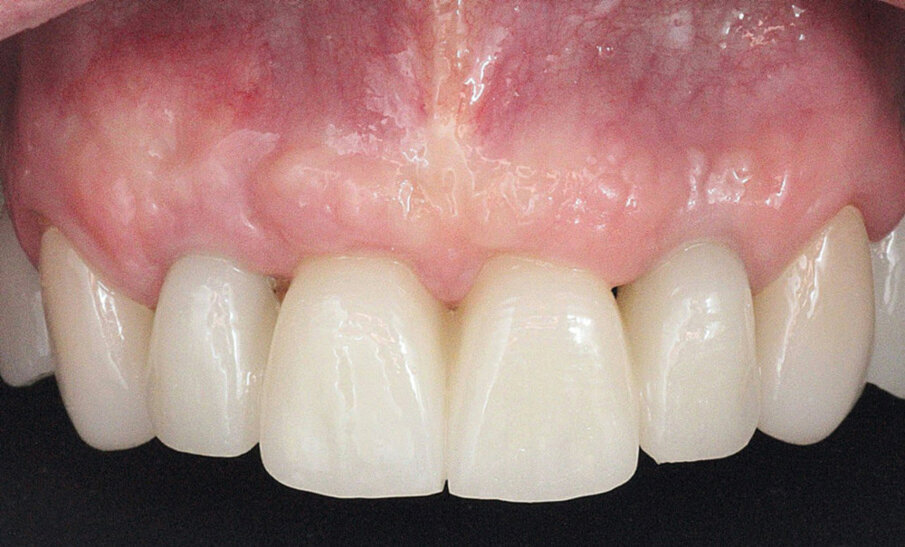

Definitivni protetski rad napravljen je nakon što je završila faza oseointegracije implantata s tri monolitna mosta od cirkonijevog dioksida (DD CubeX, Dental Direkt) proizvedenih CAD/CAM postupkom. Mostovi su pomoću vijaka pričvršćeni na titanske abutmente (PS TiB, BEGO Implant Systems) (Slike 14–16). Pravilan dosjed protetske nadogradnja se nakon umetanja potvrdio rendgenskom snimkom (Slika 17.). Kontrolni pregled nakon dvije godine u srpnju 2019. pokazao je izvrsno estetsko i kliničko stanje mekog tkiva (Slike 18–20). U području implantata radiografski se nije mogao utvrditi gubitak krestalne kosti (Slika 21.). Oba korijena središnjih sjekutića koji su ostavljeni u alveoli kao ni distobukalni korijen zuba 26 nisu pokazali nikakve znakove periapikalne upale. Pacijentica nije imala nikakvih pritužbi, a oralna higijena značajno se poboljšala tijekom razdoblja praćenja.

Slika 14. Frontalni prikaz definitivne protetske nadogradnje. Odnosi pokazuju dobru estetiku bez znakova komplikacija mekih tkiva Slika 15. Pogled na definitivni rad s desne strane. Slika 16. Pogled na definitivni rad s lijeve strane. Slika 17. Završna rendgenska slika s definitivnim implanto protetskim radom in situ. Slika 18. Frontalni prikaz definitivnog protetskog rada nakon dvogodišnjeg praćenja. Slika 19. Prikaz definitivnog protetskog rada s lijeve strane nakon dvogodišnjeg praćenja. Slika 20. Prikaz definitivnog protetskog rada s desne strane nakon dvogodišnjeg praćenja.